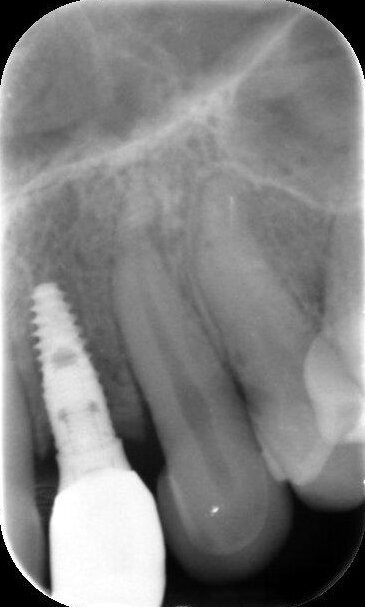

Door de regulatie van de cuspidaten naar distaal is botappositie opgetreden, waardoor bij het plaatsen van de twee implantaten een minimale botopbouw volgens een GBR-techniek noodzakelijk was (afbeelding 7-9). Via digital smile design werd de uiteindelijke vorm gesimuleerd (afbeelding 10 en 11). Er werden twee verschroefde zirkonium kronen met opgebakken porselein vervaardigd voor de implantaten en er werden facings van lithiumdisilicaat gemaakt bij de centrale incisieven en cuspidaten (afbeelding 12-17).